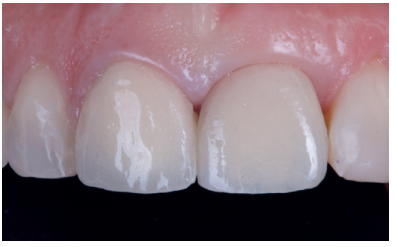

After achieving optimal tissue volume by handling the provisional (Figure 17), an initial scan of the maxilla was performed with the screw-retained provisional crown to obtain the anatomy (Figure 18). Subsequently, a second scan was performed without it, with accurate recording of the gingival contours and the emergence profile achieved (Figure 19), as well as the implant position using the scan body (Figures 20 and 21). For proper recording of the emergence profile, the provisional crown was scanned outside the mouth (Figures 22 and 23); thus avoiding having to perform the classic technique of an individualised transfer17. These records were sent to the prosthetic laboratory, which designed a post-machined sintered metal structure (Figure 24). Once the framework test had been satisfactorily carried out (Figure 25), the colour of the restoration (A2 VITA guide) was taken using a polarised light filter (Figure 26). These records were sent back to the prosthetic laboratory for completion of the implant-retained crown on the printed models (Figures 27 and 28). Prior to the placement of the definitive crown, the emergence profile of the provisional crown was compared with the final one, and the similarity observed between them (Figure 29); thus managing to preserve the profiles maintained from the day treatment was started.

After the 6-month review, excellent stability of all periimplant tissues was verified, with correct volume at the vestibular level, as well as the maintenance of optimal aesthetics and functionality (Figure 30).